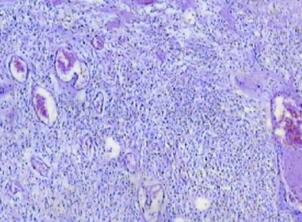

图2瘤细胞梭形或多角形,排列呈片状,血管丰富,见坏死